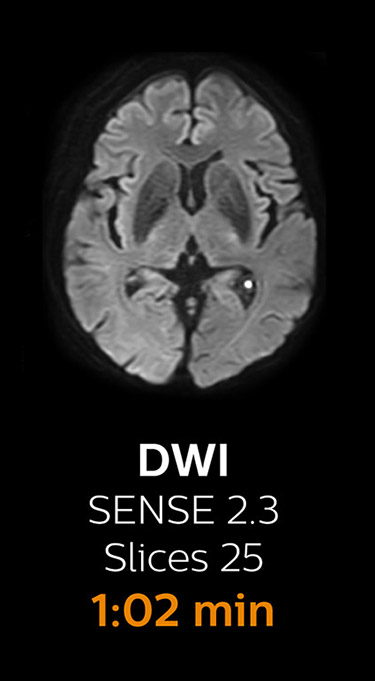

Scanning time reduction in brain MRI with Compressed SENSE

Fast MRI of brain

With Compressed SENSE, the scan time for the routine brain examination at KNC was reduced from 15:48 to 10:19 minutes, which corresponds to 35% reduction.

Ingenia 3.0T CX

Scan time 15:48 min.

Brain with Compressed SENSE

Ingenia 3.0T CX

Scan time 10:19 min.